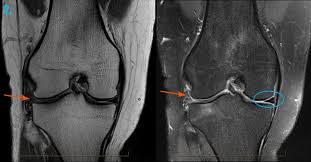

An MRI of the knee joint is one of the most advanced imaging methods used to detect hidden injuries that may not appear on X-rays. It provides detailed images of ligaments, cartilage, tendons, and soft tissues, helping doctors diagnose conditions like ligament tears, meniscus damage, inflammation, or early joint degeneration. Early detection allows specialists to recommend the right treatment and prevent further complications. If you are experiencing knee pain, swelling, or limited movement, a professional scan can provide clear answers—contact Marris Medical UK today at +44 203 011 1788 to book your MRI appointment and receive accurate diagnosis and care.